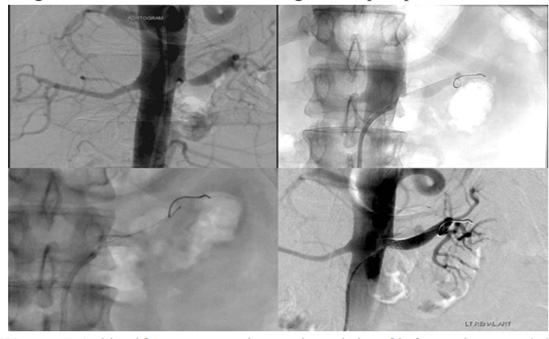

Renal artery angioplasty and stenting is when our interventional radiologist can open the narrow renal arteries to restore normal blood flow. This is done through a small puncture site rather than surgery. The interventional radiologist guides a catheter to the diseased portion of the blood vessel where they can expand the blood vessel and flatten the plaque causing the blockage with a balloon. If needed, the narrowed vessel can also be stented.